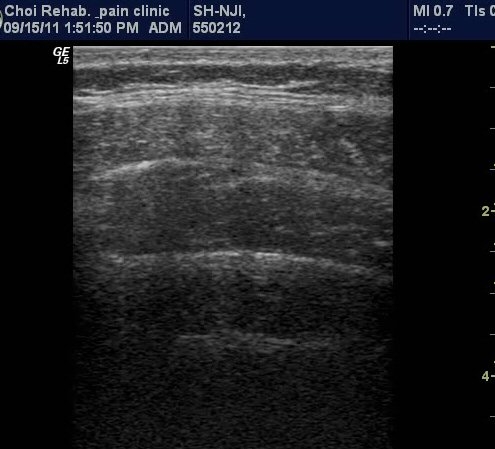

µ¿¿µ»ó 1, 2). ŽÃËÀÚ¸¦ Ä¡°ñ »óºÎ(ŽÃËÀÚ 2)¿¡ ´ë°í ¹æ±¤À» °üÂûÇÑ »óÅ¿¡¼­ °ñ¹Ý ¹Ù´ÚÀÇ ±ÙÀ°À»

¼öÃàÇÏ¿© ¹æ±¤À» ¸Ó¸® ÂÊÀ¸·Î µé¾î ¿Ã¸®´Â ¸ð½À(µ¿¿µ»ó3).